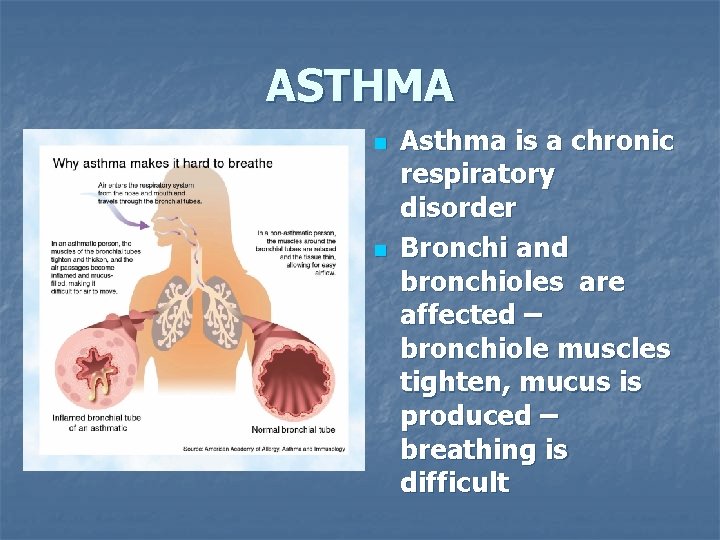

ASTHMA n n Asthma is a chronic respiratory disorder Bronchi and bronchioles are affected – bronchiole muscles tighten, mucus is produced – breathing is difficult